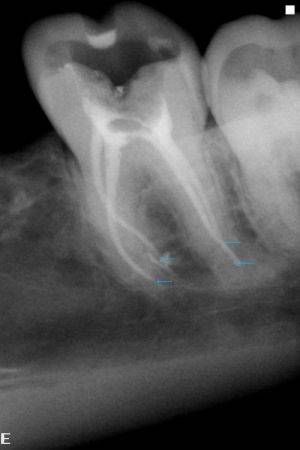

Врачи отмечают, что воспаление пульпы, или пульпит, является распространенной стоматологической проблемой, требующей внимательного подхода. Основными симптомами заболевания являются интенсивная боль в зубе, особенно при воздействии температуры или механическом раздражении, а также возможное появление отека и покраснения десен. Причинами пульпита могут быть кариес, травмы зуба или осложнения после стоматологических процедур. Для диагностики врачи используют рентгенографию и клинические тесты, позволяющие оценить состояние пульпы. Лечение может варьироваться от консервативных методов, таких как пломбирование, до более сложных, включая эндодонтическое лечение. Важно обратиться к стоматологу при первых признаках заболевания, чтобы избежать серьезных осложнений и сохранить зуб.

Диагноз «воспаление пульпита» ставится после осмотра и сбора анамнеза. Используется также рентгеновское обследование. Иногда выясняют порог электрической возбудимости пульпы. При осмотре выявляется наличие кариеса, реакция на горячее, холод, кислое. Часто отмечают размягченные ткани. Зондирование полости может дать разный результат. В острой форме пульпит дает резкую болезненность. Если болезнь хроническая, то болезненность меньше. Реакции на постукивание нет. Острое воспаление на рентгене не заметно. Хронический этап болезни на рентгене покажет расширенную периодонтальную щель.

Электро-возбудимость пульпы постепенно падает. На острой фазе заболевания ЭОД 20-40мкА, при хронической — около 70мкА. Как не спутать пульпит с похожими стоматологическими заболеваниями?

Распознать пульпит можно в ходе инструментального осмотра у стоматолога. Врач выявляет кариозную полость с открытой пульпой. При касании к ней наблюдается резкая боль. Чтобы получить точные данные о характере и степени тяжести заболевания, необходимо пройти цифровую рентгендиагностику.